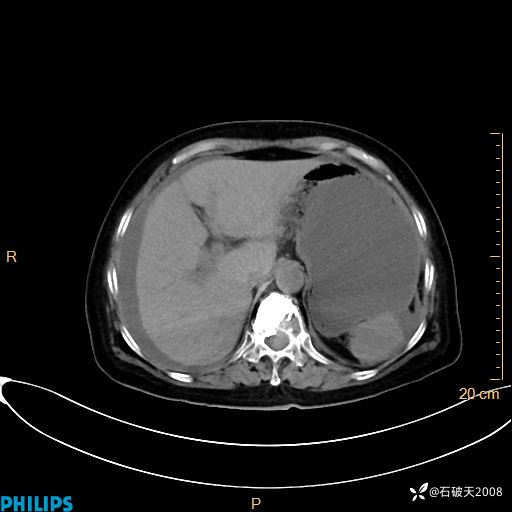

动脉期